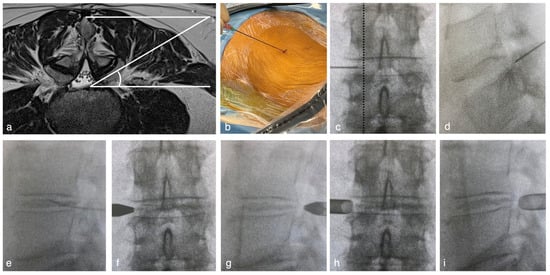

- The entry point was determined to be 8–13 cm from the midline to acquire 45° from the horizontal line (Figure 1a). The spinal needles were inserted from the entry point until they reached the lateral aspect of the superior articular process (SAP) (Figure 1b). The needle tip was inserted into the foramen and slid along the ventral part of the facet joint (Figure 1c,d). Needle entry into the intervertebral disc should be more internal than the medial line of the cranial and caudal pedicles in the A-P and lateral views. The needle was advanced. The nucleus pulposus was stained with saline, indigo carmine, and an imaging agent (Figure 1e). Preoperative discography clarifies the difference between herniated fragments and other soft tissues under an endoscopic view.

- The needle was replaced with a guidewire, and an approximately 3 cm incision was made at the entry point. A pencil dilator was then inserted along the guidewire (Figure 1f,g). The guidewire was removed after the tip of the pencil dilator touched the superior facet. A bevel-type cannula was inserted using a pencil dilator (Figure 1h,i). Finally, the endoscope was introduced.